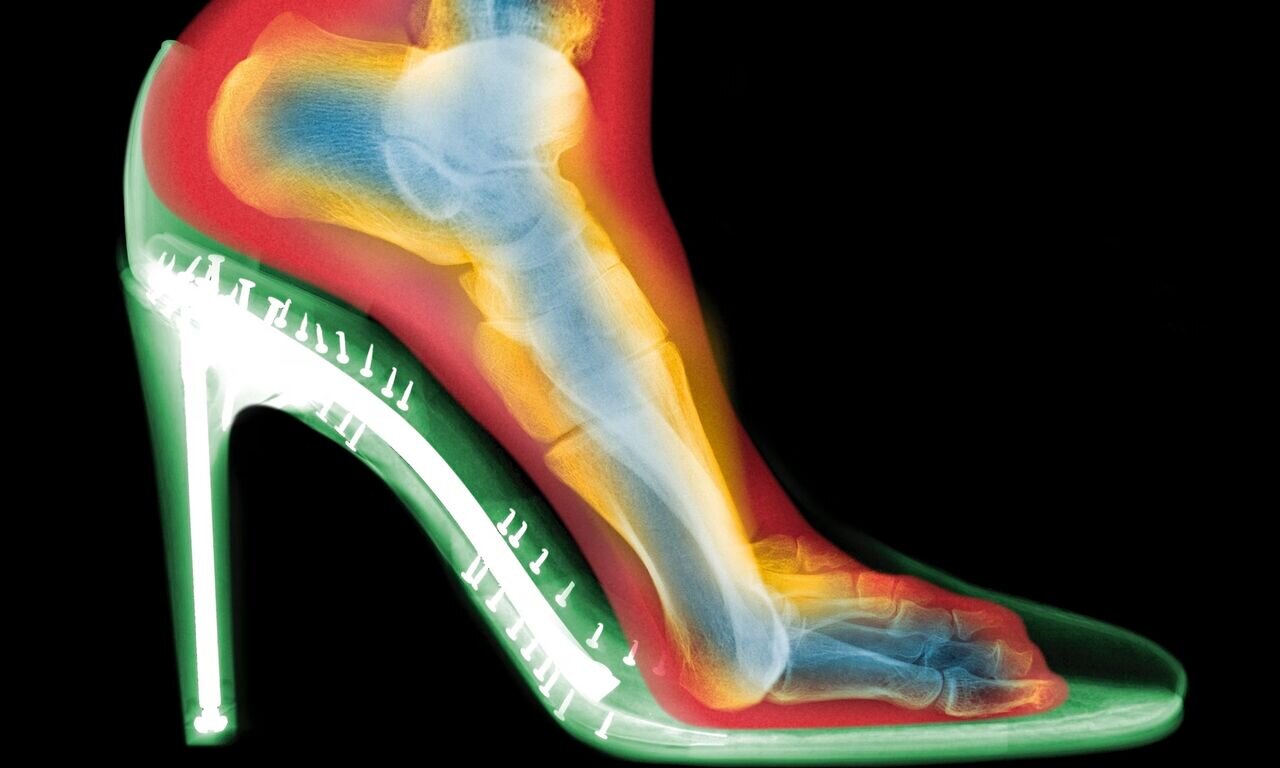

«اگر ۱۵ سال پیش از من میپرسیدید، میگفتم کاملاً بیمعناست؛ همهچیز ژنتیکی است و کفشها مسئول هیچ مشکلی نیستند.»؛ این را اندرو گلدبرگ (Andrew Goldberg)، متخصص ارتوپدی پا و مچ پا در بیمارستان ولینگتون لندن میگوید. اما او پس از دیدن اسکنهای سهبعدی از پاهای افراد در حین پوشیدن کفش، نظر خود را کاملاً تغییر داد.

اسکنهای سهبعدی چه نشان دادند؟

گلدبرگ دو اسکن از پای یک فرد تهیه کرد: یکی بدون کفش و دیگری با کفش پاشنهبلند. تفاوتها چشمگیر بود:

فشردگی انگشتان : انگشتان پا در کفش به هم فشرده شده بودند؛

انحراف شست پا (بونیون) : مفصل انگشت شست به طرف بیرون متمایل شده بود؛

انگشتان چنگالی : انگشتان کوچکتر برای حفظ تعادل، حالتی قفلشده و خمیده به خود گرفته بودند.